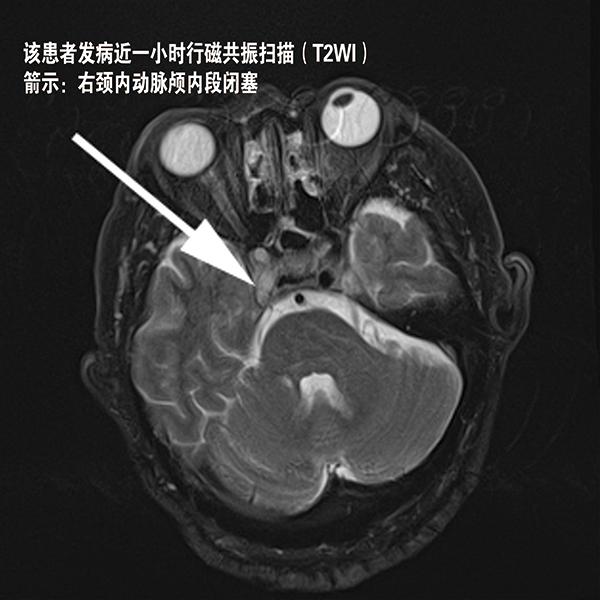

我院投巨资引进国际最先进东芝Vantage Elan15T超导磁共振成像系统。该系统适用于全身系统的不同疾病,尤其无造影剂动态血管成像,是业内领先的心脏冠脉成像的技术的应用。

使该系统最适合复杂循环系统的动态研究成为最早发现微小出血灶脑梗塞的唯一影像学手段。其对全身肿瘤病灶的敏感性,尤其是对脑与脊髓疾病的敏感性和特异性,成为神经系统疾病诊断的应用之最,并且具有一般磁共振无法比拟的优势。